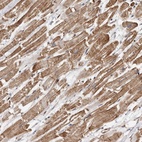

Immunohistochemical staining of human heart muscle shows moderate membranous and cytoplasmic positivity in myocytes.